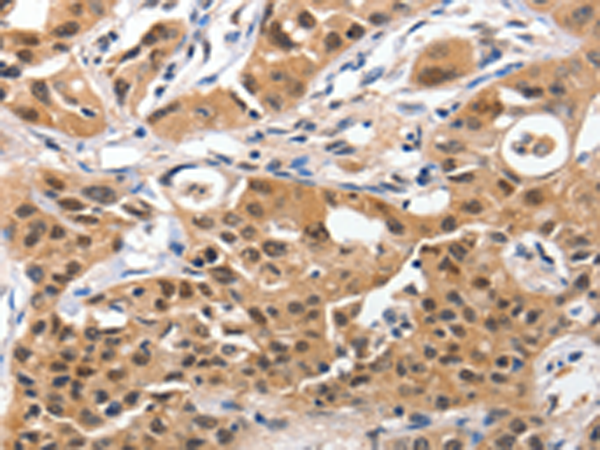

分类: 科研抗体货号: P11043别名: TBM; leB; MUC5; mucin应用: IHC反应种属: Human